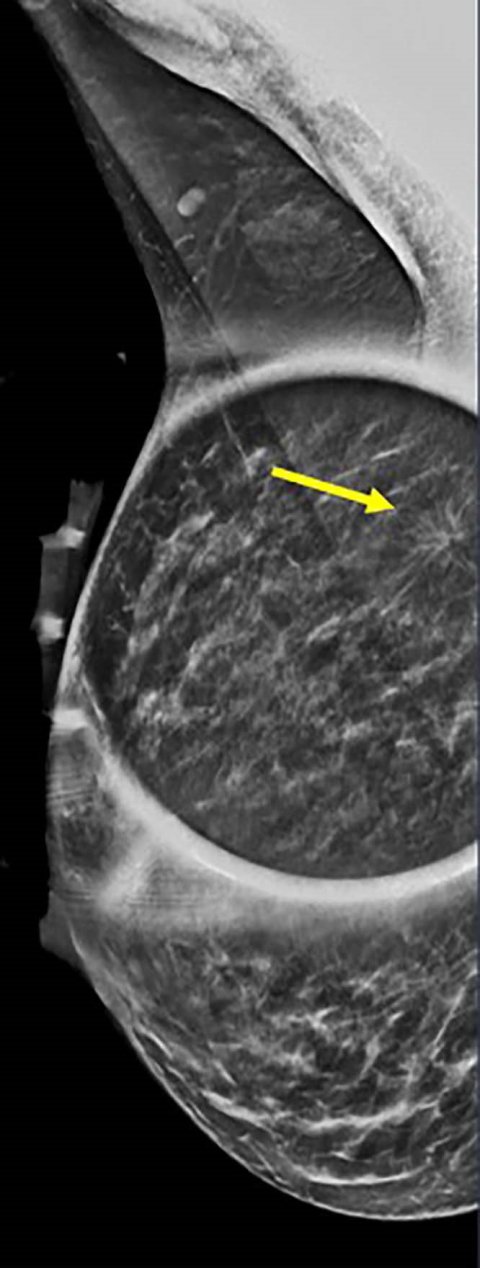

Image credit: Stamatia Destounis, M.D., and RSNA

A total of 1,799 breast cancers were diagnosed in 1,290 women, aged 18 to 49. Annual breast cancer diagnoses in this group ranged from 145 to 196, with a mean age at diagnosis of 42.6 years (range 23-49). Of these, 731 (41%) were detected on screening and 1,068 (59%) on diagnostic evaluation. There were 1,451 invasive cancer cases (80.7%), and 347 (19.3%) non-invasive cancer cases. “Most of these cancers were invasive, meaning they could spread beyond the breast, and many were aggressive types—especially in women under 40,” Dr. Destounis said. “Some were ‘triple-negative,’ a form of breast cancer that is harder to treat because it doesn’t respond to common hormone-based therapies.”